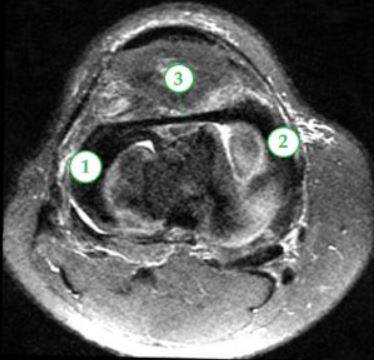

КТ мягких тканей колена: стрелки указывают на места, где расположены нечетко видимые мениски

МРТ мягких тканей коленного сустава: 1 и 2 - мениски латеральный, медиальный, 3 - межменисковая связка